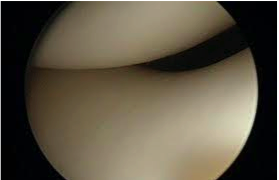

Blick auf das Patellofemoral Gelenk (Kniescheiben-Oberschenkelgelenk) während einer Arthroskopie, gesunder, glatter Knorpel.